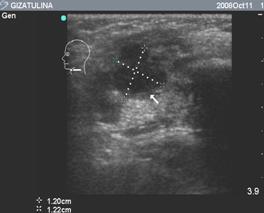

Инструментальные методы включали ультразвуковое исследование (эхографию) лимфоузлов. Использовались аппараты с конвексными и линейными датчиками с частотой 7,МГц с цветным допплеровским картированием (ЦДК). Данный метод применялся в группе исследования. При помощи УЗИ, в В-режиме оценивали размер лимфоузла, его форму, соотношение слоев, однородность эхоструктуры. Проводили оценку кровотока в области ворот, наличие или отсутствие очагов деструкции. При эхографии лимфоузлы - это образования овальной или округлой формы, расположенные в подкожной клетчатке и мягких тканях. Обычно хорошо дифференцируются основные части: корковый, мозговой слой и ворота лимфоузла, с впадающими сосудами. Эхоструктура лимфоузлов представлена на рис. 2

А Б

Рис. 2. А) Структура лимфоузла в норме,

Б) Структура при остром лимфадените